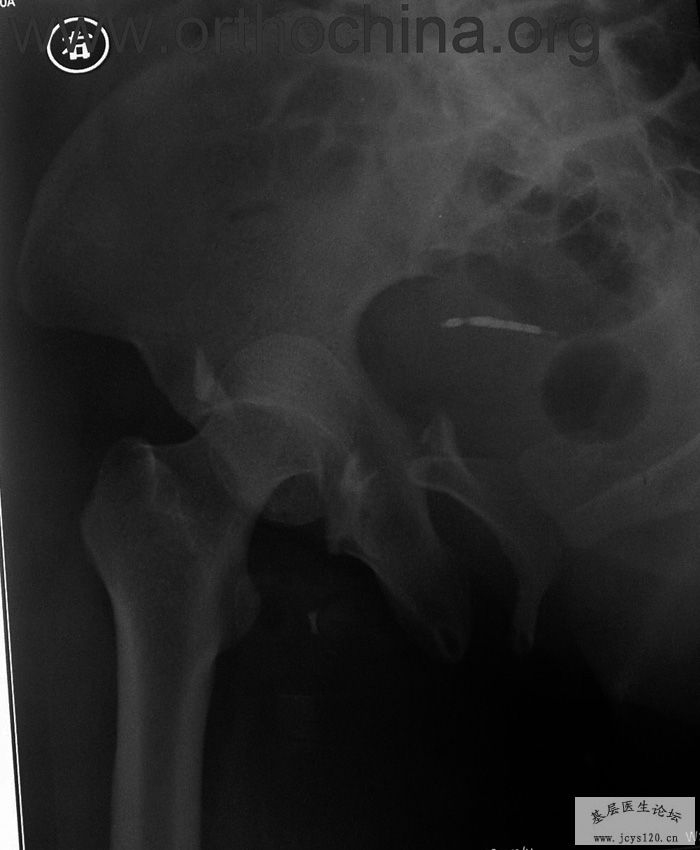

患者,女,28岁,车祸中骨盆轧伤后疼痛功能障碍1小时。查体:休克外貌,烦躁不安。头颈胸腹无异常,脊柱无异常,两下肢血供及感觉正常。骨盆挤压分离试验阳性。阴道、尿道、直肠、腹内脏器无损伤。住院后抗休克、骨牵引及对症治疗1周后,行前后联合入路手术。股骨头骨折复位后用可吸收螺钉固定,骶髂关节、髋臼前后柱、对侧耻骨上下支用骨盆重建钛板固定,术中出血1200ML,手术时间8小时。部分图片如下: